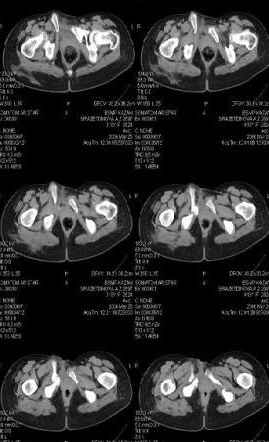

Предоставляю срезы. Если пациентку функционально ничего не беспокоит, стоит ли навязывать ей лечение.

Для уточнения диагноза ниеобходимы обзорные рентгенограммы таза (прямая и inlet), Кт срезы на уровне переломов для определения степени сращения и решения вопроса о методе оперативного восстановления анатомии (делать ли остеотомию, низводить ли задние отделы), ни о какой "остеотомии выступающих отломков" тем более у девочки 18 лет речи быть не может.

При более детальном распросе, наверное, удастся обнаружить и другие жалобы, либо они появятся при увеличении нагрузок. Как представляется, задачей лечения будет являться восстановление целостности и стабильности тазового кольца. Оптимальным вариантом может быть низведение левой половины таза, затем реконструкция передних отделов. Варианты выполнения репозиции и фиксации - тема отдельного разговора.

Если пациентка не собирается жить половой жизнью и вообще собирается в моностырь, то пожалуй, я бы согласился с Вами и навязывать лечение не стал.

Но если девочка более активна в жизни, я бы рекомендовал ликвидировать укорочение и вернуть тазу естественную форму.